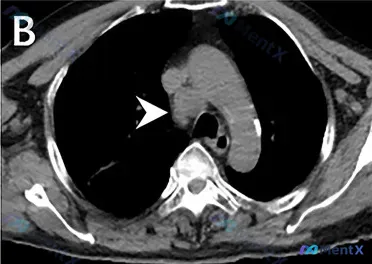

- 胸部CT(纵隔窗):右侧气管旁(2R/4R组区域)类圆形/分叶状软组织密度团块,边界清,密度均匀,未见钙化或中心坏死;病灶推压周围结构(主动脉弓、气管),但无明显侵袭性包绕;主动脉壁见点状钙化,余大血管、气管、食管、椎体未见明显异常

病灶紧邻主动脉弓和上腔静脉,如果贸然穿刺,可能刺破血管导致大出血;而且增强CT还能看强化方式——均匀强化更提示淋巴瘤,环形强化则更支持结核/脓肿,对后续活检方案(比如是否需要预留流式细胞术样本)也很关键。